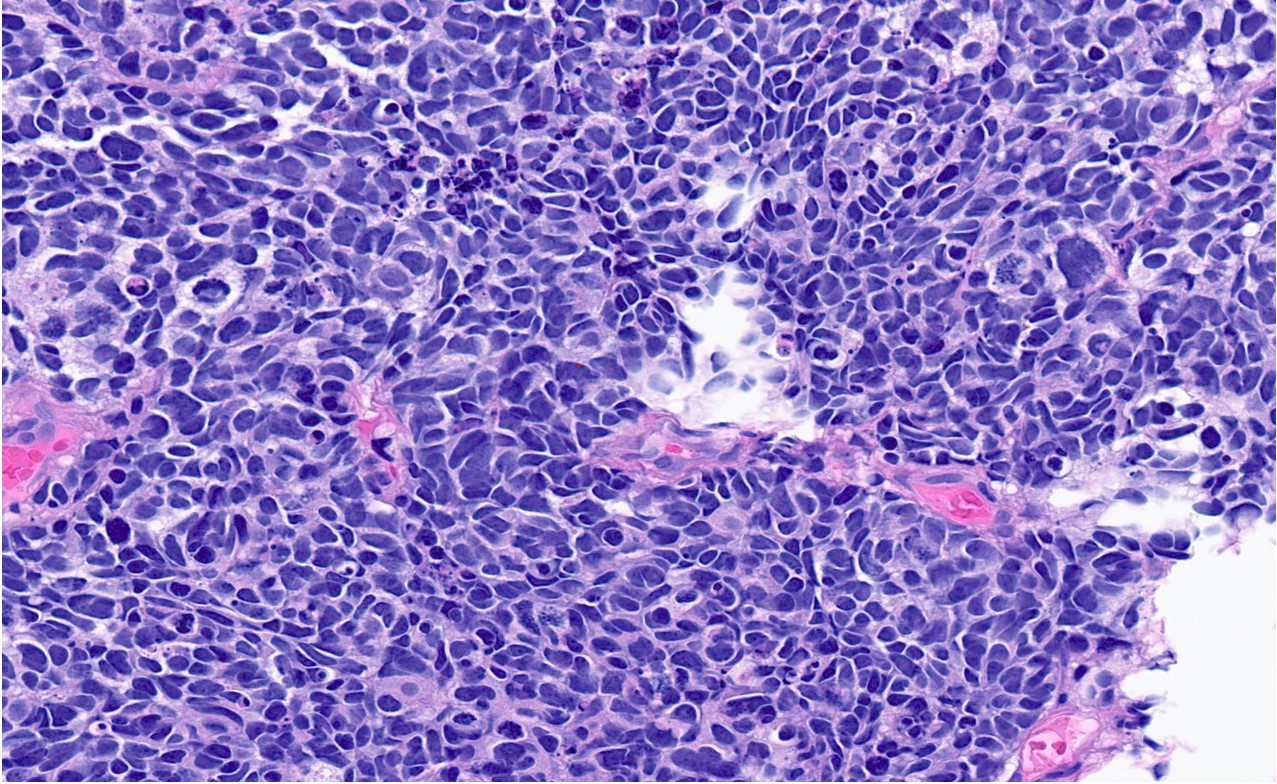

Patolojik İnceleme: Biopsi örneği mikroskop altında incelenir. Küçük hücreli nöroendokrin karsinomu, özellikle hücresel morfolojisi, hızlı bölünme ve sıkı hücre kümeleri ile belirgin olur.